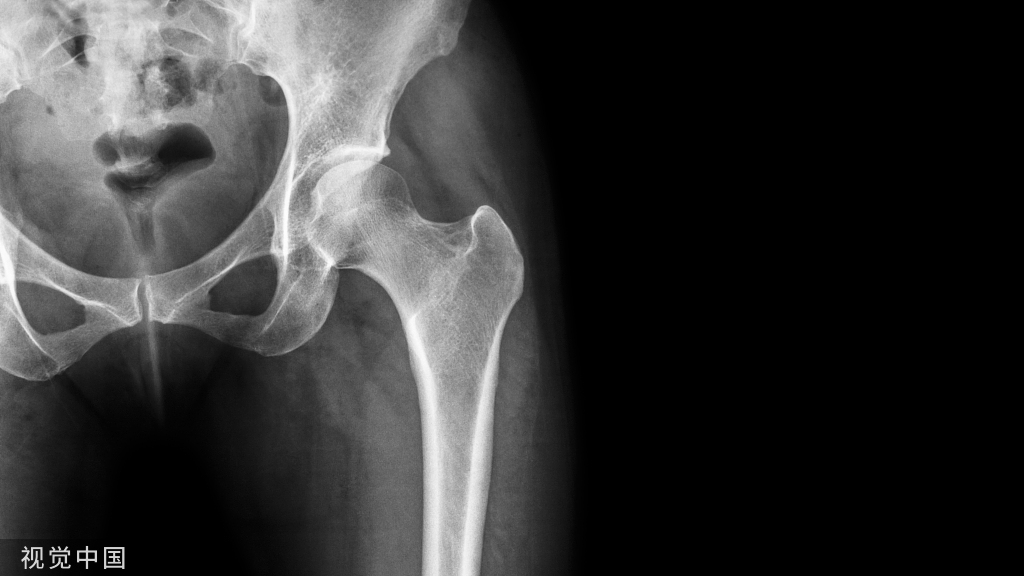

EMG检查:可见足底内、外侧神经传导速度减慢、潜伏期延长及踝内侧神经或踝外侧神经所支配的足小跖肌震颤。X线检查:可发现及了解踝关节及跟骨骨折愈合情况,了解照成骨性压迫的原因。CT检查:双侧对比有助于发现跖管内的囊肿及肿瘤等。